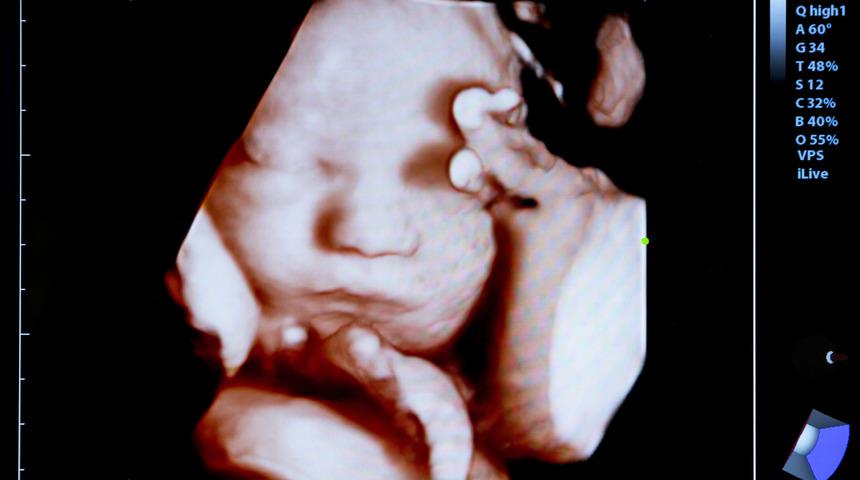

Bebeğinizi doğmadan görün

Tıpta yaşanan gelişmeler bebek bekleyen aileleri de sevindiriyor. 4 boyutlu ultrasonografiyle bebeğin cinsiyetinin yanı sıra anne karnındaki görüntüsünün vesikalık bir resim gibi alınabildiğini açıklayan Kadın Hastalıkları ve Doğum Uzmanı Opr. Dr. Lale Zeynep Kanmaz, "Sadece resimle kalmayıp, bebeğinizin o an neler yaptığı da gözleyebilirsiniz. Sağlığı hakkında birçok ipucu elde edebilirsiniz" dedi.

Dr. Kanmaz, 4 boyutun ultrasonografide gelinen son nokta olduğunu söyledi. Gebelikte ultrasonun yerinin büyük önem taşıdığına dikkat çeken Kanmaz, "Bu alandaki yeni gelişmeler ultrasonun hamilelik sırasında anne ve bebek sağlığı açısından önemini perçinliyor. En son yenilik ise 4 boyutlu ultrason. Bu cihaz ile bebeğin anne karnındayken neler yaptığını izlemek, bebeğin anne karnındaki görüntülerinden fotoğraf albümü oluşturmak mümkün. Resmi gören anne ve baba bebeğin kime benzediği konusunda yorum bile yapabiliyor. Parmağını emen, esneyen, esnerken ağzını kapatan, ayak parmağını emmeye çalışan, gülümseyen, diğer ikizinin başını okşayan bebeklerini görebilmek ailelere büyük keyif veriyor" diye konuştu.

"Bebeğinizin doğmadan arşivini yapın. 4 boyutlu ultrason ile bebeği izlemenin dışında isteğe bağlı CD'ye kayıt alınıp daha sonra izlenmesi, saklanarak ileride bebeğe izlettirilmesi de mümkün. Bu teknolojinin daha önceki 3 boyutlu ultrasonlardan farkı bebeği ve hareketlerini anında görebilmeyi ve bunu CD'ye kaydederek hoş bir anı olarak saklanmasını sağlaması. Parmak emen, esneyen, esnerken ağzını kapatan, ayak parmağını emmeye çalışan, gülümseyen, kaşlarını çatan, diğer ikizinin başını okşayan bebekleri görebilmek, ailelerle bebek arasında farklı bir duygusal bağ oluşturuyor."

Annenin bebeğini doğmadan görebilmesi dışında, '4 Boyutlu Ultrason' yardımıyla dudak-damak yarığı, spina bifida, parmak anomalisi gibi anormalliklerin daha net tespiti mümkün. Dr. Kanmaz, "Cihazın diğer bir fonksiyonu da doppler ile ölçüm yapabilmesidir" diyerek, "Bu sayede de gelişme geriliği, hipertansiyon, çoğul gebelikler, gün geçmesi gibi yüksek riskli gebelikler sağlıklı bir şekilde izlenebiliyor" ifadelerini kullandı.